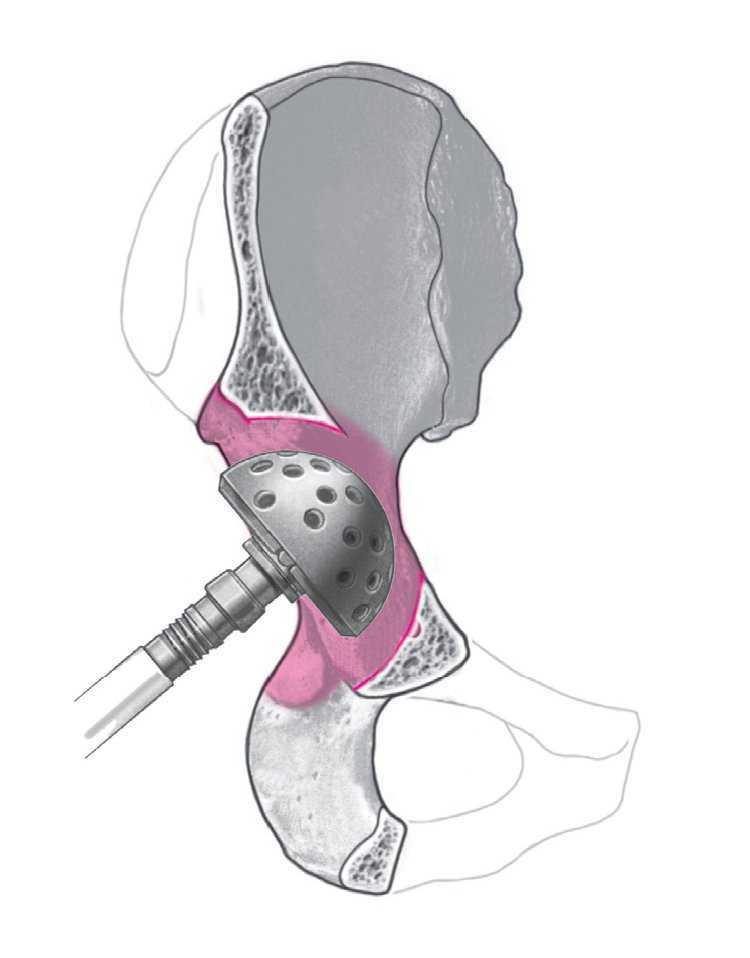

El cótilo utilizado en este trabajo es el AllofitSTM, que consiste en un componente acetabular pressfit de Protasul-Titan que se caracteriza por una pared de sólo 3 mm. Mediante un aumento a nivel ecuatorial de 2 mm y una disminución del diámetro a nivel polar de un mm, se obtiene el principio de pressfit según Morscher14,15 (fig. 1).

Figura 1. Cótilo AllofitSTM con exposición del aplanamiento polar y del pressfit ecuatorial de 2 mm.

La superficie del cótilo dispone de unos 1.200 punchones en disposición radial de 1 mm que aumentan la superficie de contacto hasta un 80%. En el borde del cótilo se hallan hasta seis anclajes para asegurar la estabilidad rotacional en el hueso. Estos anclajes salen perpendiculares y se reparten hacia la periferia (fig. 1), lo cual facilita un mejor asentamiento al colocar el implante. Con cada golpe el cótilo progresivamente se ancla más hasta el pressfit necesario. Nosotros utilizamos el implante AllofitSTM en cirugía de revisión con un pressfit de 4 mm, con lo cual elegimos el implante de una talla superior a la última fresa.